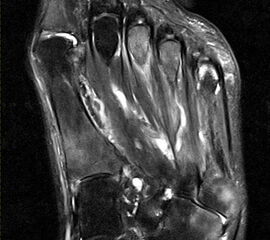

Degenerative Veränderungen im Bereich der Fußwurzel und tarsometatarsal sind wiederum häufig schmerzhaft. Es zeigen sich die klassischen morphologischen Veränderungen der Gelenkdegeneration (Gelenkspaltverschmälerungen, Osteophyten, Zystenbildungen, subchondrale Knochenmarkveränderungen) (Abb. 16) und häufig Zeichen der entzündlichen Aktivierung (Erguss, Synovialitis, Kapselschwellung).

Die Diagnose ist meist schon klinisch und radiographisch zu stellen. Eine relativ häufige Differenzialdiagnose, die klinisch wie eine mediale tarsometatarsale Degeneration imponieren kann, ist die Tendinopathie der Tibialis anterior Sehne (Abb. 17).